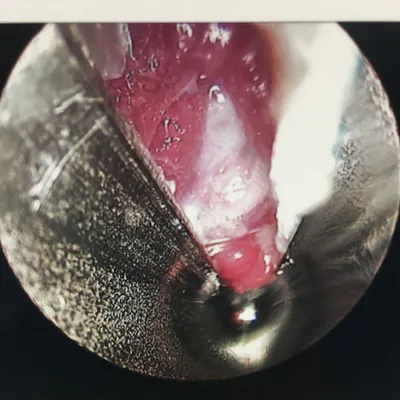

Pictures during an endoscopic plantar fasciotomy or release. The medial band of the fascia is visualized on the left. The two right pics are during the release of the band.